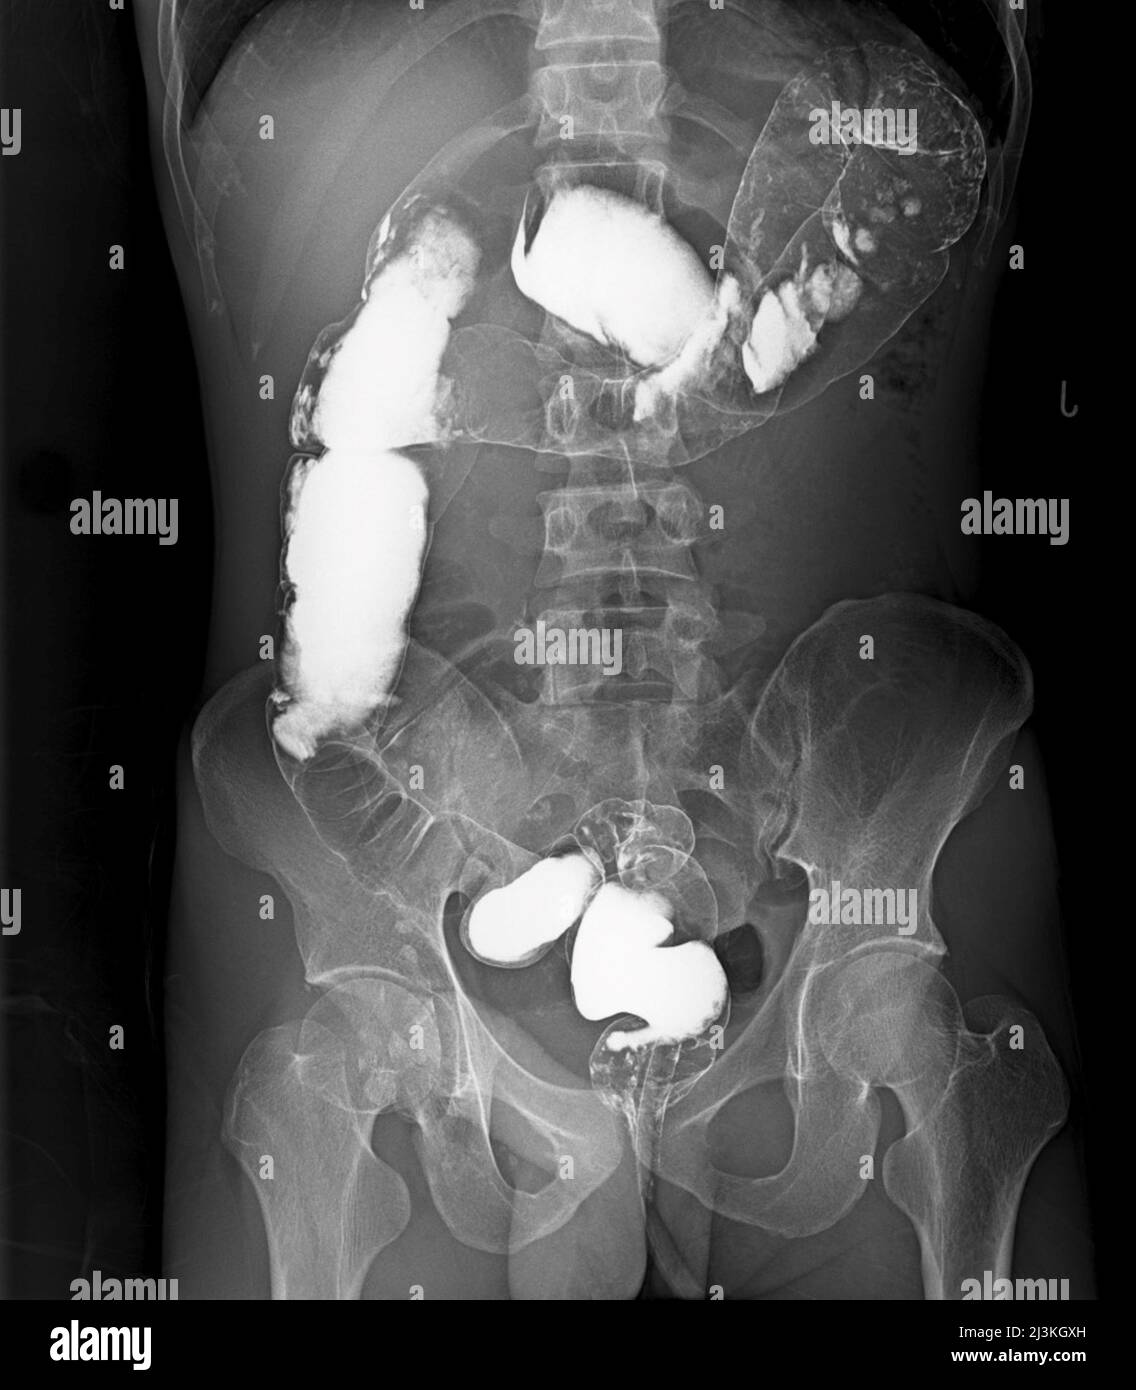

Diagnostic Imaging of the Abdomen XRay, Ultrasound, CT, MRI Colon White Spots These small, shallow ulcers usually look like white spots on the colonoscopy and can appear in the early stages of the. during endoscopy, white spots (ws) are sometimes observed around benign or malignant colorectal tumors; lesions appear as slightly elevated whitish or yellowish adherent plaques, often multiple and sometimes. colon erosions are small, shallow sores or ulcers. Colon White Spots.

Abnormal calcifications in a pelvic radiograph The BMJ Colon White Spots colon erosions are small, shallow sores or ulcers on the lining of your colon, or large intestine. It usually begins as small clumps of cells. These small, shallow ulcers usually look like white spots on the colonoscopy and can appear in the early stages of the. colon cancer typically affects older adults, though it can happen at any. Colon White Spots.

Abdominal Xray Interpretation (AXR) Radiology OSCE Geeky Medics Colon White Spots during endoscopy, white spots (ws) are sometimes observed around benign or malignant colorectal tumors; lesions appear as slightly elevated whitish or yellowish adherent plaques, often multiple and sometimes. colon erosions are small, shallow sores or ulcers on the lining of your colon, or large intestine. These small, shallow ulcers usually look like white spots on the colonoscopy. Colon White Spots.